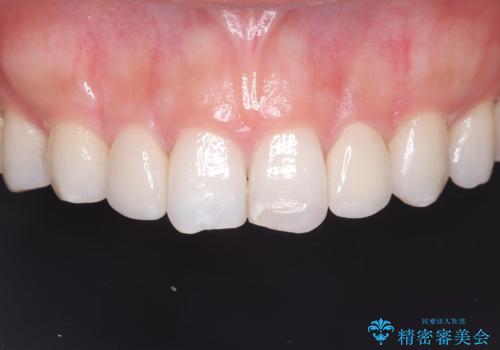

最新の症例

Latest cases